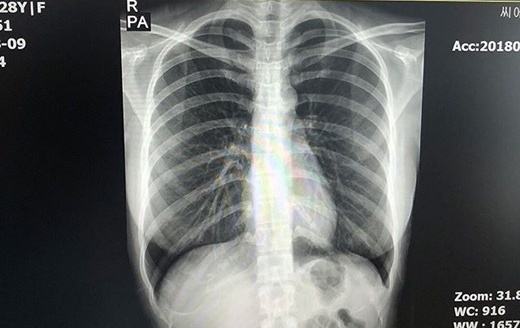

DongA đưa tin người mẫu Choi Somi vừa công bố một số hình ảnh kiểm tra từ bệnh viện trên SNS cá nhân. Choi Somi đã chụp X-quang vùng ngực tại bệnh viện. Kết quả y tế cho thấy không hề có vật thể lạ ở vùng ngực.

| Người đẹp Hàn bức xúc vì tin đồn phẫu thuật thẩm mỹ. |

| Cô tới bệnh viện kiểm tra và công bố kết quả trên mạng xã hội. |